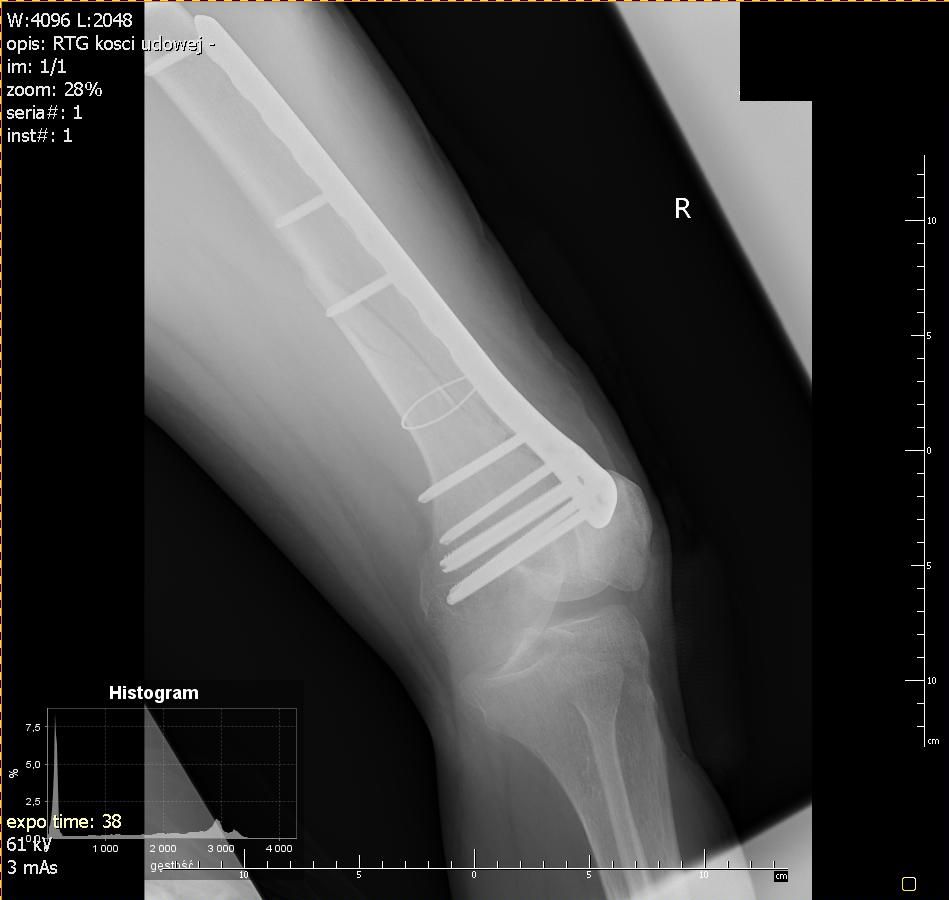

Przyjechałem na SOR. W wielkim skrócie to rejestracja, rentgen i diagnoza: złamanie spiralne 1/3 dalszej trzonu kości udowej prawej i zakwalifikowany do operacji.

Operacja zaczęła się około 13, a o 15 byłem na sali pooperacyjnej. Lekarze coś tam do mnie gadali, maszyny pikały, pielęgniarka co chwilę mnie szturchała bym oddychał. Gdyby nie to, że byłem taki senny to bym jej coś powiedział ale nie miałem sił. Wtedy chciałem ją zabić :) Koło godz. 17 już bardziej kumałem. Przyszli lekarze i powiedzieli mi, że wszystko jest ok, że mam w nodze płytkę, śruby i drut tytanowy. Z tym ostatnim przed operacją był problem bo był tylko stalowy ale na szczęście udało się w ostatniej chwili odszukać tytanowy drut i okręcić nim kość.

Ktoś może zapytać jaka to różnica między tytanem, a stalowym implantem? W przypadku implantów stalowych nie mogę korzystać z rezonansu magnetycznego. Chodzi o to, że w stalowym obiekcie wytwarzają się prądy wirowe pod wpływem silnego pola elektromagnetycznego z rezonansu magnetycznego, a to zaś powoduje duże nagrzanie elementów stalowych. Dzięki implantom tytanowym nie będę musiał ich wyjmować oraz będę mógł bez przeszkód robić rezonans. To tyle z "wykładu" o fizyce.